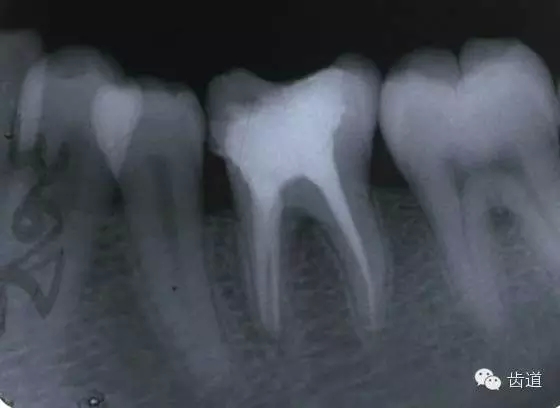

左上5牙頸部側(cè)穿

開髓時鉆針進(jìn)入方向與根管走行方向不一致,鉆針需改變方向時。

根管壁穿孔多在根管彎曲處。